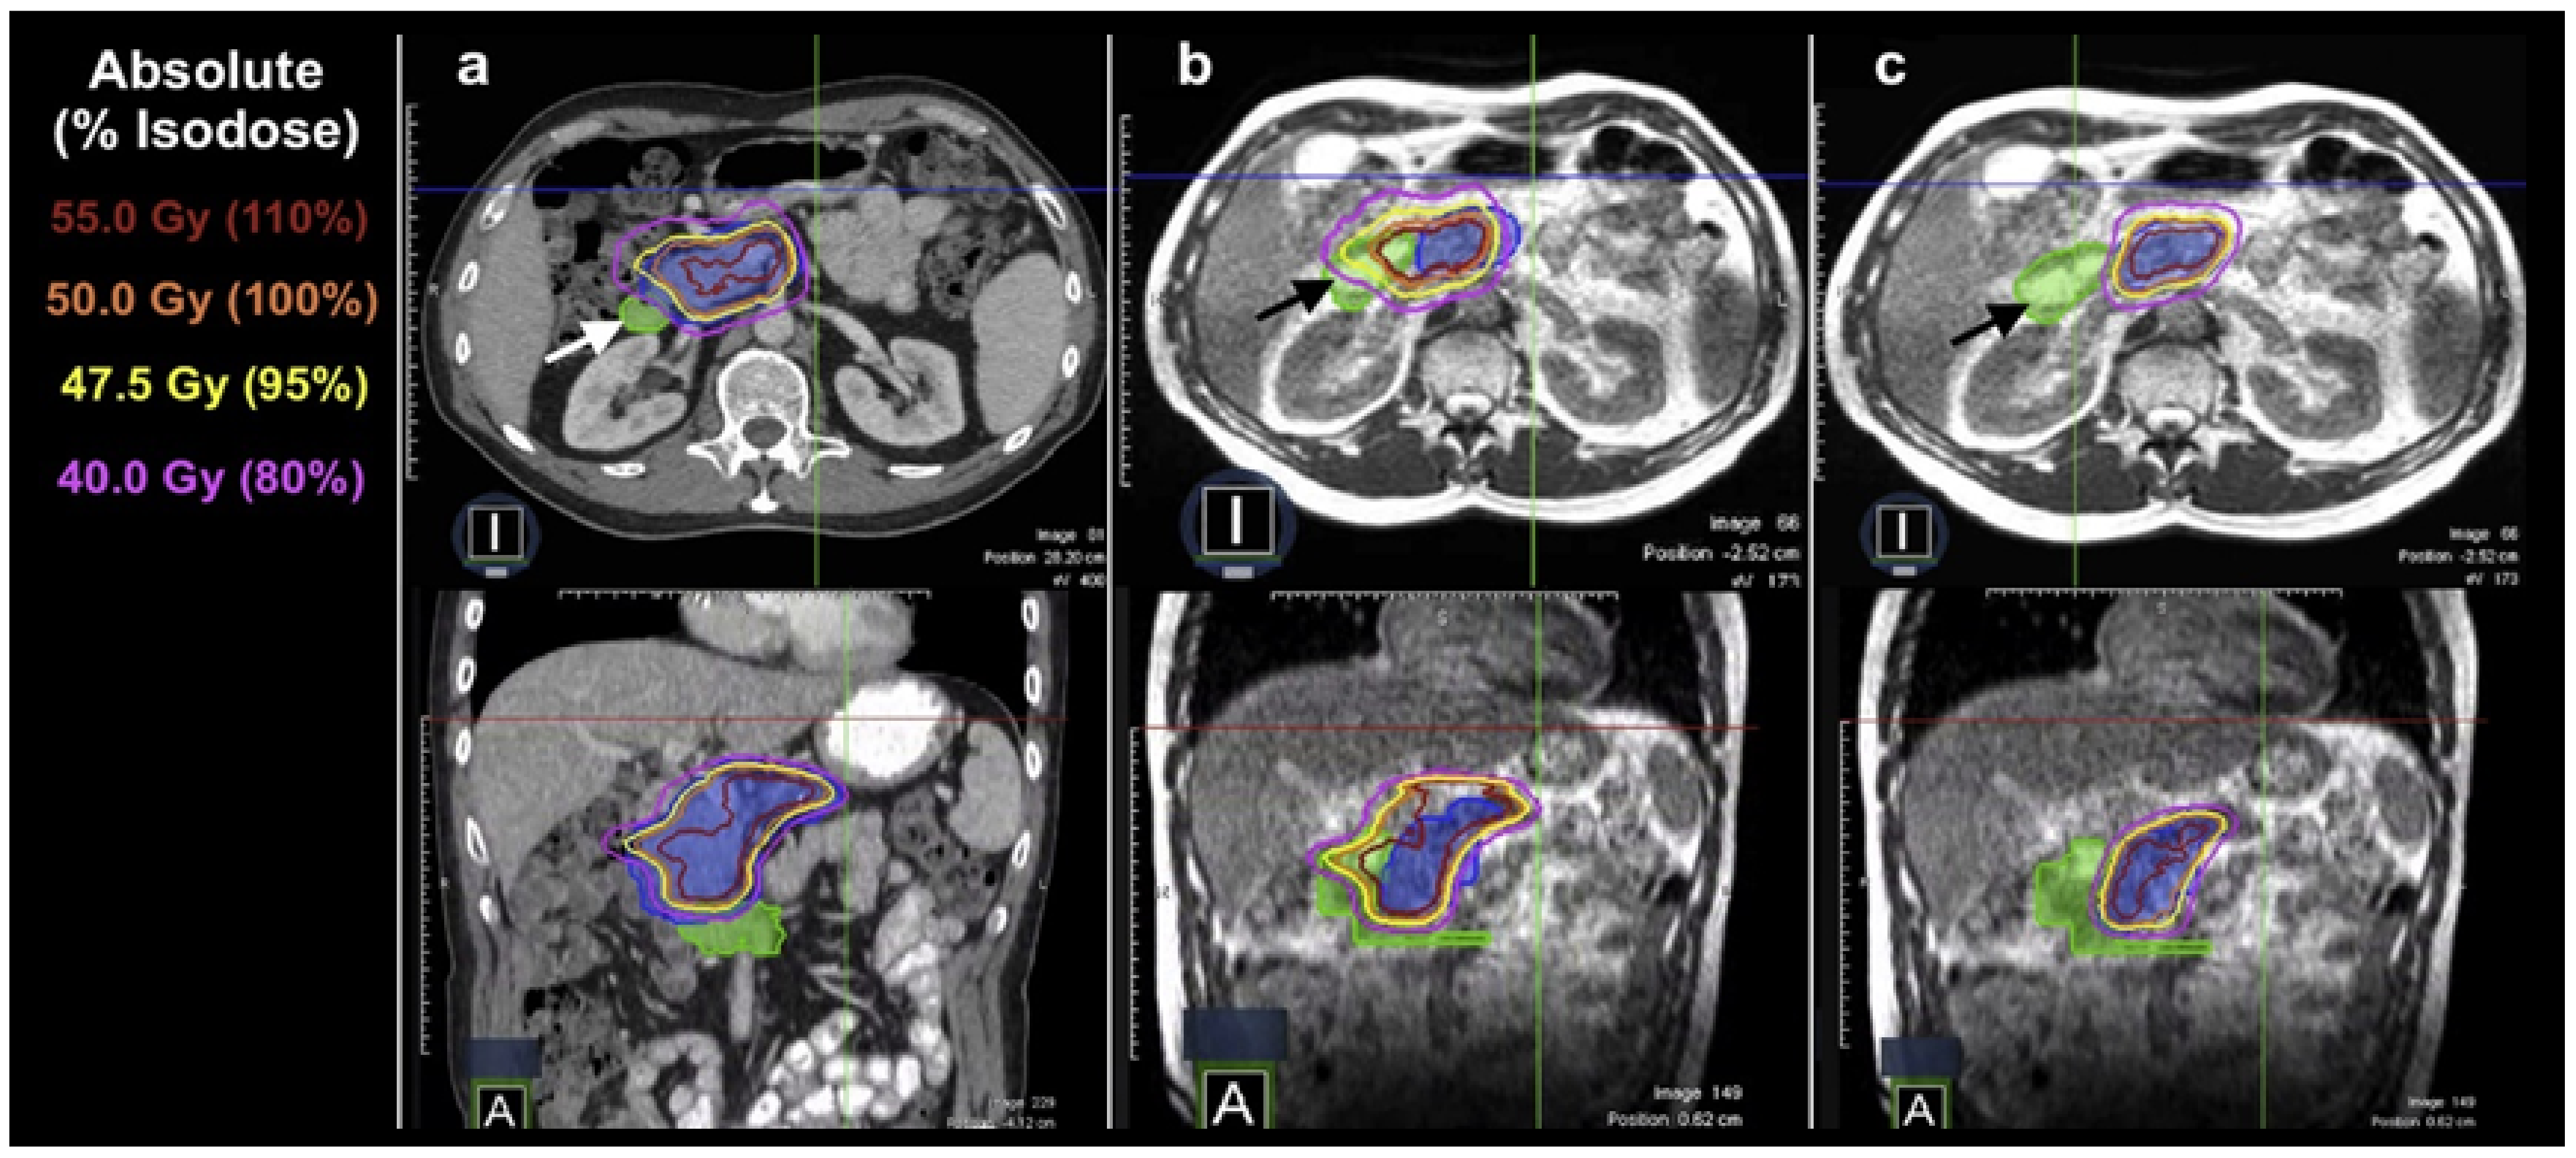

5.5. Pancreatic Cancer, Liver Cancer, and Abdominal Oligometastasis

- Henke, L.; Kashani, R.; Yang, D.; Zhao, T.; Green, O.; Olsen, L.; Rodriguez, V.; Wooten, H.O.; Li, H.H.; Hu, Y.; et al. Simulated Online Adaptive Magnetic Resonance–Guided Stereotactic Body Radiation Therapy for the Treatment of Oligometastatic Disease of the Abdomen and Central Thorax: Characterization of Potential Advantages. Int. J. Radiat. Oncol. Biol. Phys. 2016, 96, 1078–1086. [Google Scholar] [CrossRef]